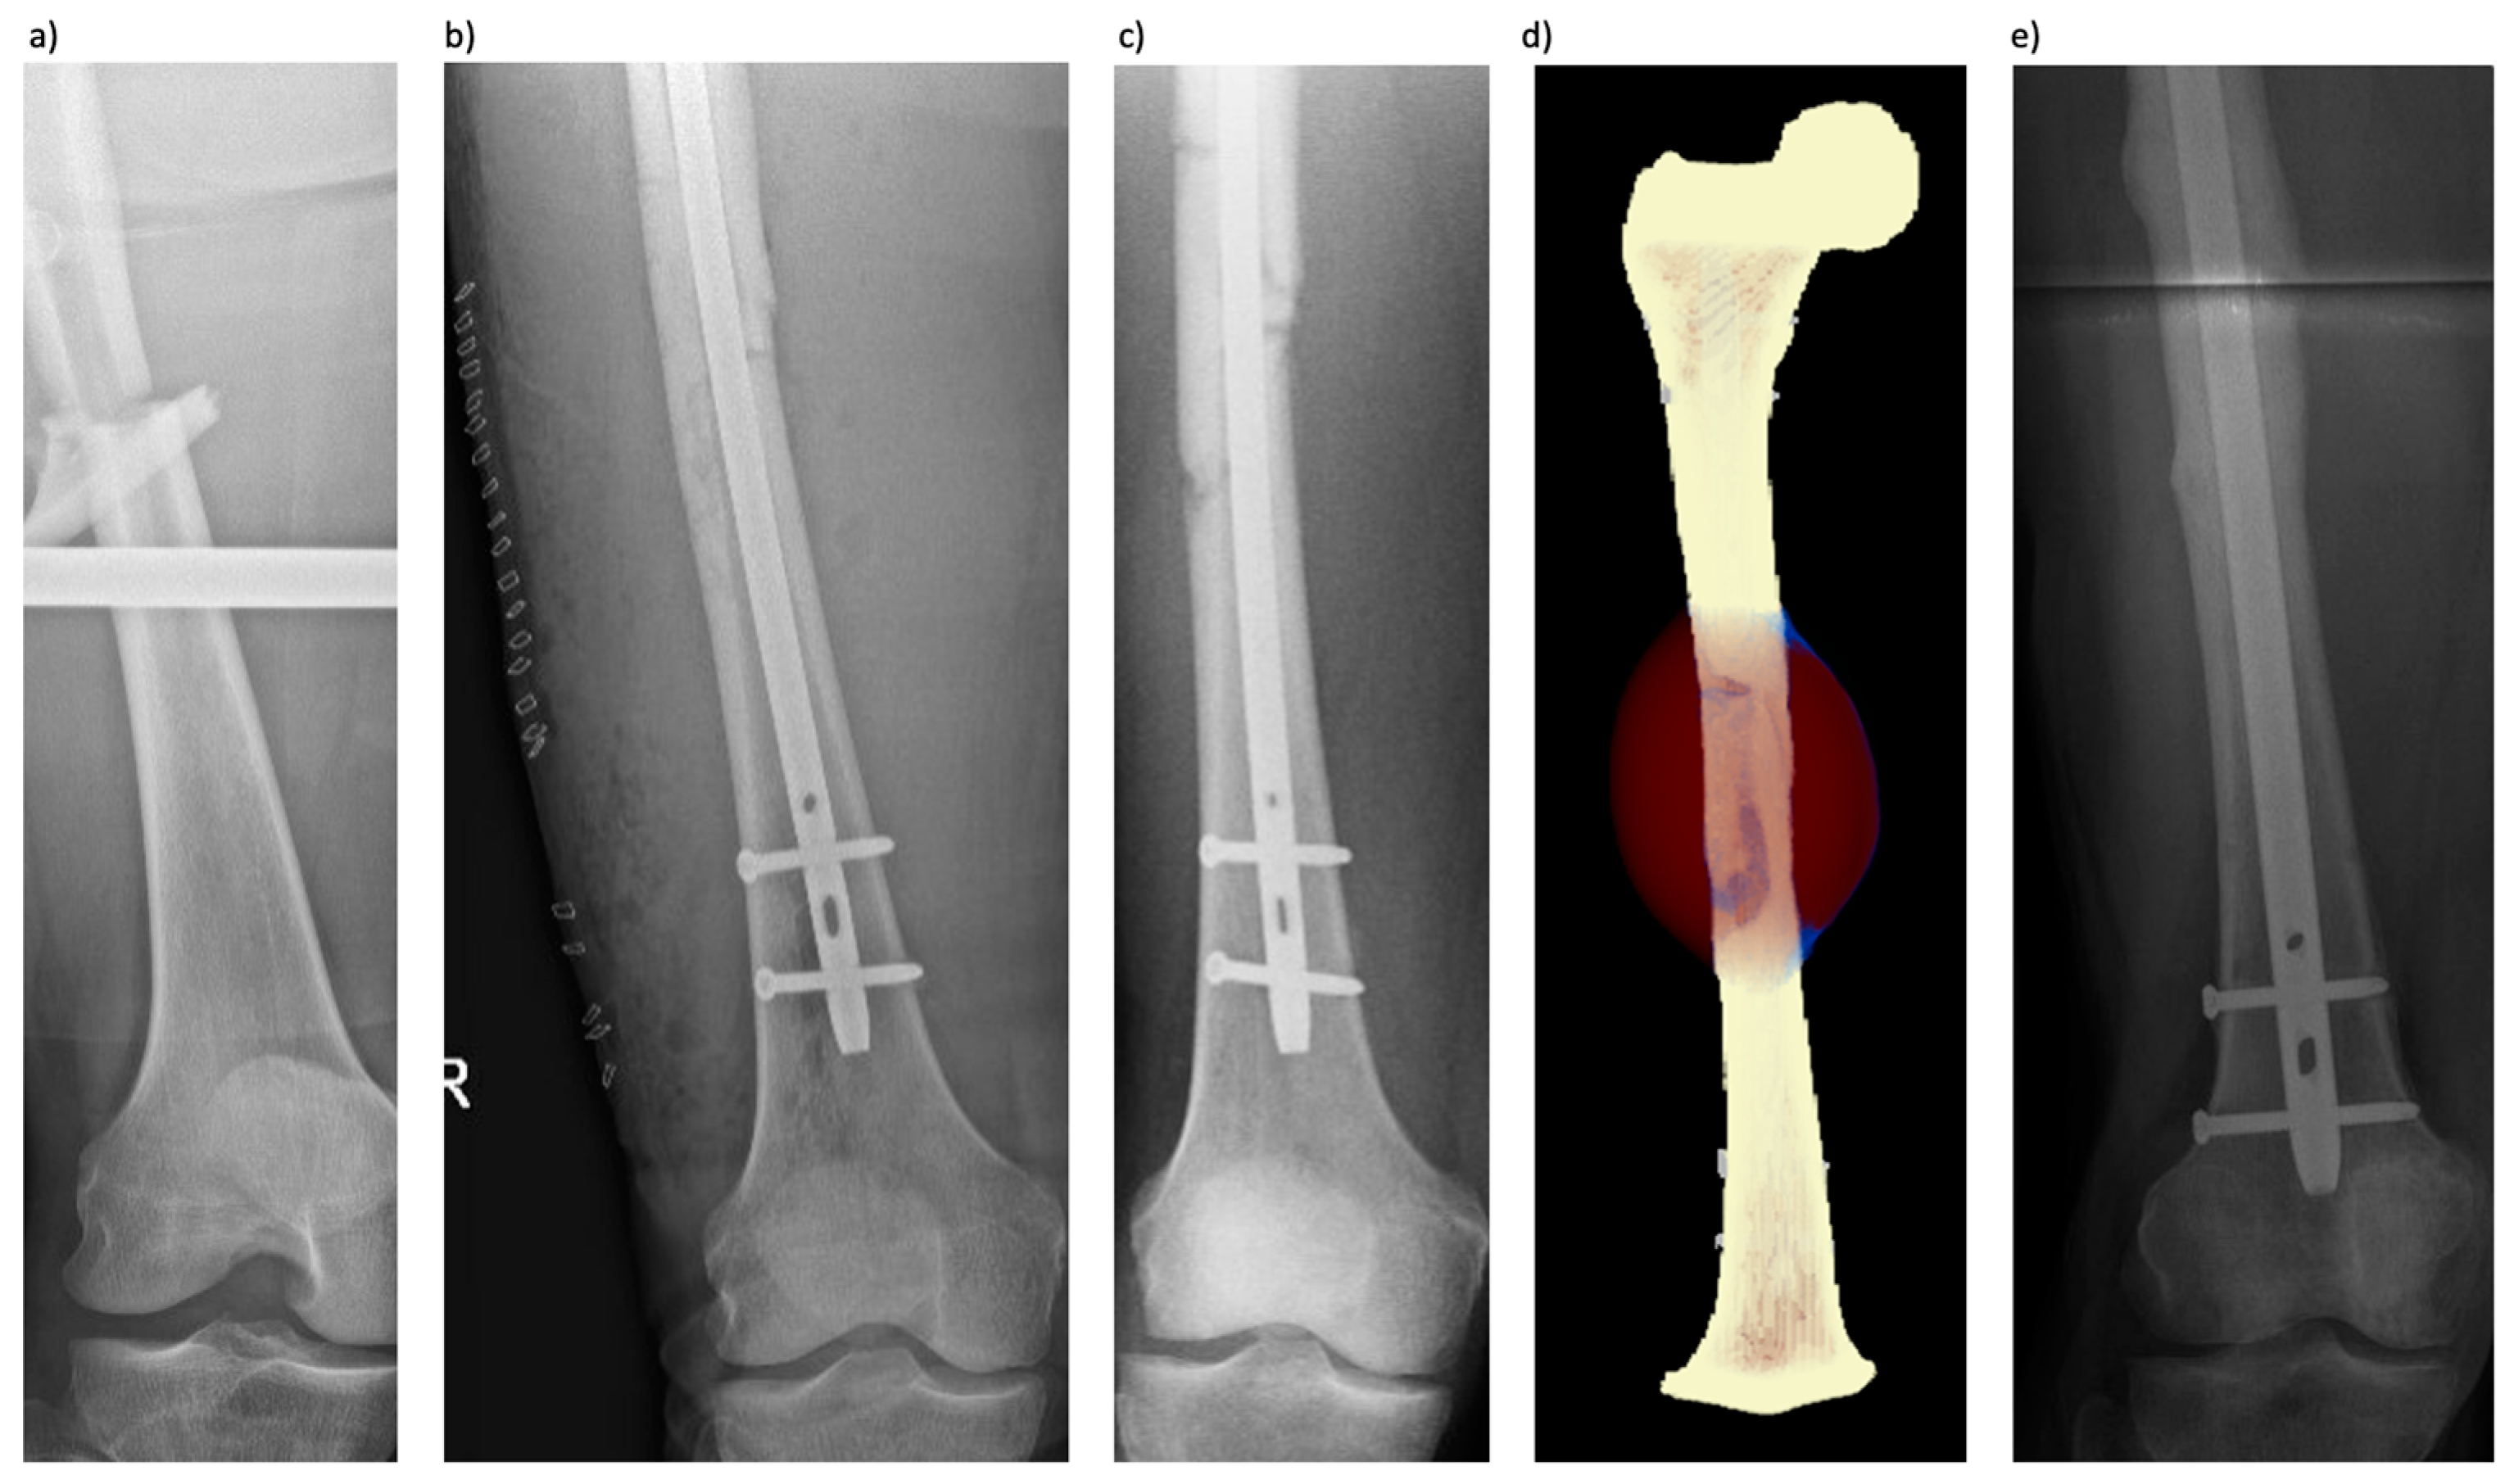

3.2. Patient 2 (Femoral Fracture)